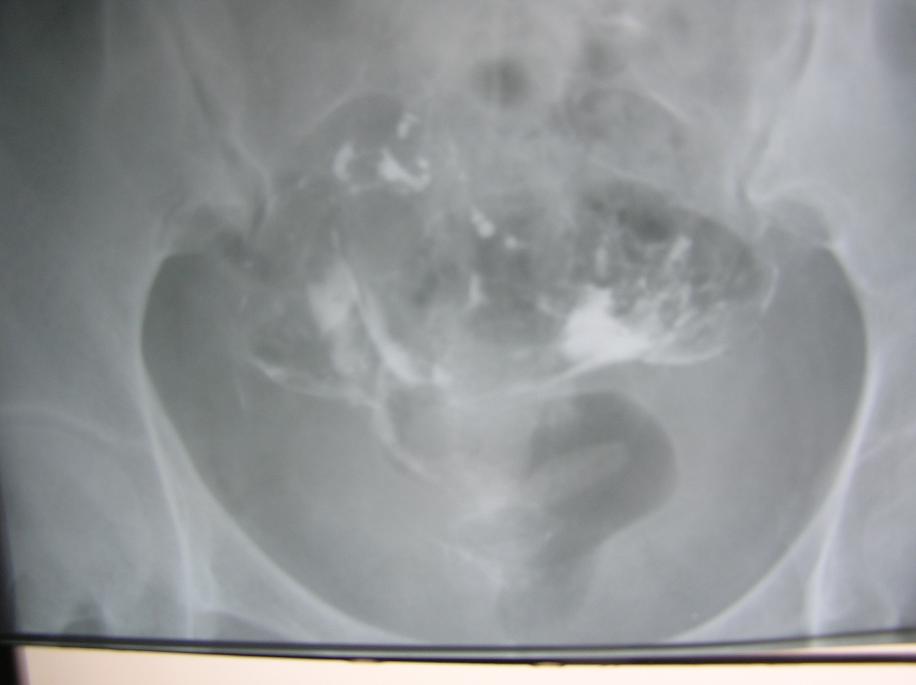

以下是引用杀毒软件在2009-3-27 18:22:00的发言:[br]比较严重的---宫腔粘连,整个宫腔看起来似---双角子宫,弥散像造影剂多在宫旁及输卵管旁,右侧输卵管僵直,壁上有小突起。[br][br]首选考虑----双侧慢性输卵管炎----〔宫腔粘连,输卵管周围粘连〕。 病人应该有很重盆腔炎。[br][br]因为单纯宫腔粘连,输卵管表现可保持正常,但此例子宫及输卵管都有明显改变的表现----不能排除---结核,建议---ppd。[br]

以下是引用随光逐影在2009-3-28 7:59:00的发言:[br]考虑为:1)鞍形子宫。2)宫腔炎。3)双侧慢性输卵管炎。